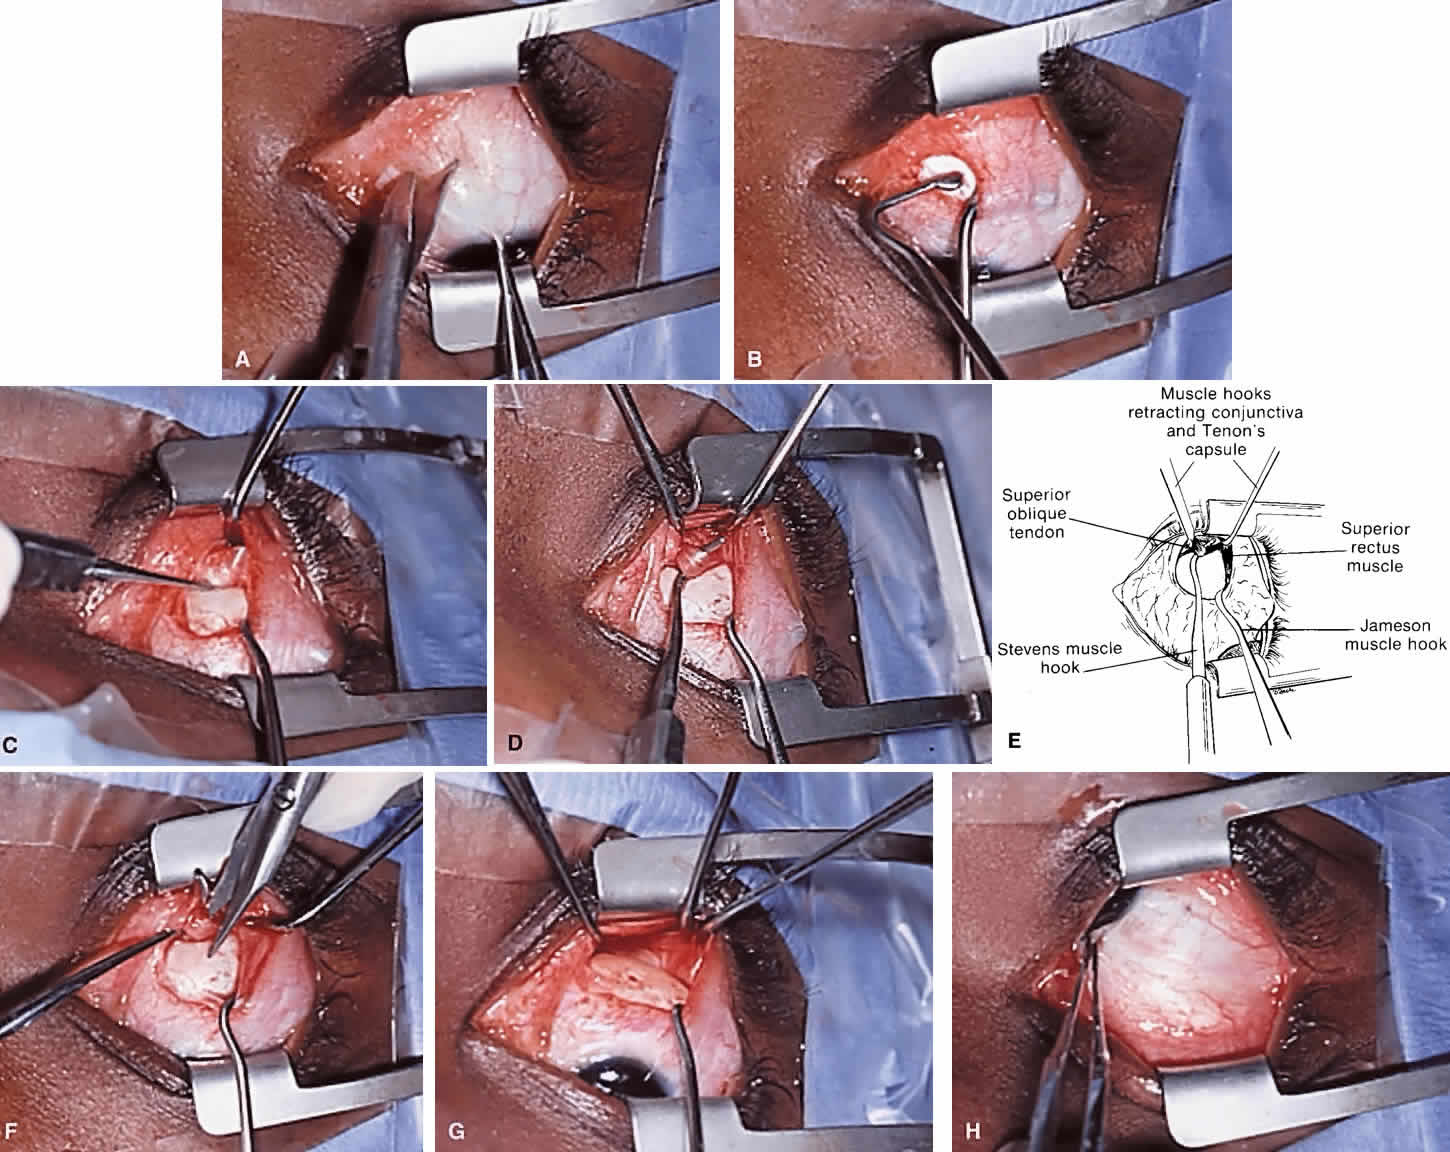

The superior oblique tendon tuck is best performed near the tendon's insertion as described by McLean.48 The surgical procedure is performed through a superior temporal cul-de-sac approach (Fig. 4). With the globe depressed, an incision is made through the conjunctiva and Tenon's fascia just temporal to the lateral border of the superior rectus muscle and parallel to the corneoscleral limbus. The superior rectus muscle is engaged on a muscle hook and the globe adducted and positioned in maximal depression. The lateral rectus muscle may also be used to assist positioning the globe. Using two small muscle hooks, the conjunctival incision is stretched open posteriorly in a triangular fashion. The lateral border of the superior rectus muscle is elevated and displaced medially. The globe is then examined for the glistening, white fibers of the superior oblique tendon running flush against the sclera and directed anteromedially. The anterior portion of the reflected tendon typically inserts under the lateral border of the superior rectus muscle, 5 to 7 mm posterior to its insertion. However, this location may vary, and anatomic anomalies are common (Fig. 5).12,37,47,48 The superior oblique tendon looks very different near its scleral insertion than 10 mm more proximally, where it becomes cordlike and enters Tenon's fascia after passing under the belly of the superior rectus muscle. Inexperienced surgeons have mistaken the lateral portion of the tendinous insertion of the superior rectus muscle for the superior oblique tendon (Fig. 6).49 However, the superior rectus muscle travels toward the orbital apex and contains prominent anterior ciliary blood vessels, whereas the superior oblique tendon is directed toward the trochlea and is usually avascular. In addition, direct traction on the superior oblique tendon can easily be palpated at the trochlea by pressing a finger over the eyelid in the superior nasal quadrant of the orbit.10 This is a reliable sign that the tendon (and not some other structure) has been engaged on the muscle hook.

|

After the superior oblique tendon has been positively identified, it is gathered on a Stevens tenotomy or other muscle hook with a small tip. This maneuver is most readily accomplished by passing the hook over the tendon with its tip parallel to the sclera and pointed medially. Direct visualization of the tendon is essential, in that blind sweeping can be hazardous. A superior temporal vortex vein usually exists near the posterior insertion of the superior oblique tendon and the optic nerve is within reach. In addition, it is important to avoid passing the muscle hook into orbital fat because its release into the sub-Tenon's space predisposes the eye to develop an adherence syndrome postoperatively.50